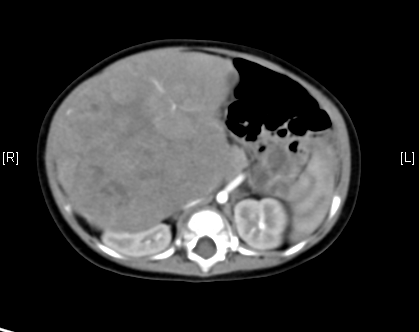

上腹部增强CT:考虑肝母细胞瘤可能性大。

平衡期